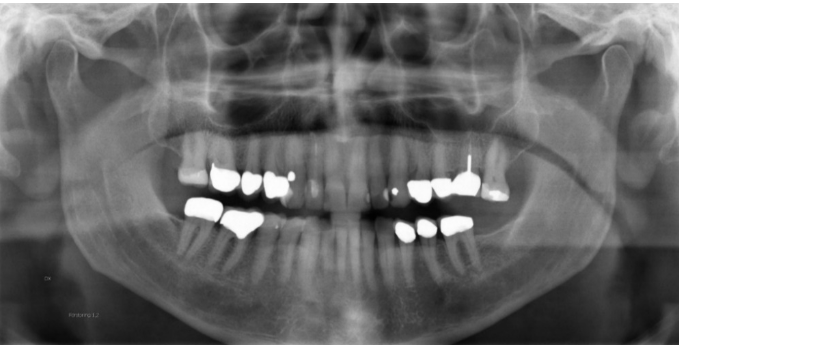

Tungan ej lyft upp mot gommen – luftspalt bildas vilket ger en mörkare bild över rotspetsarna.

”Ledsen bild”

- Lutar huvudet bakåt – lyfter upp hakan. Bilden blir ”ledsen”.

- Överkäksincisivernas rotspetsdel hamnar utanför det skarpa skiktet.

- Underkäksincisiverna ses tydligare.

”Glad bild”

- Lutar huvudet framåt – sänker hakan. Bilden blir ”glad”.

- Underkäksincisiverna hamnar utanför det skarpa skiktet.

- Tungbenet tecknar sig över mandibeln.

- Käkledhuvudet kan hamna utanför bilden